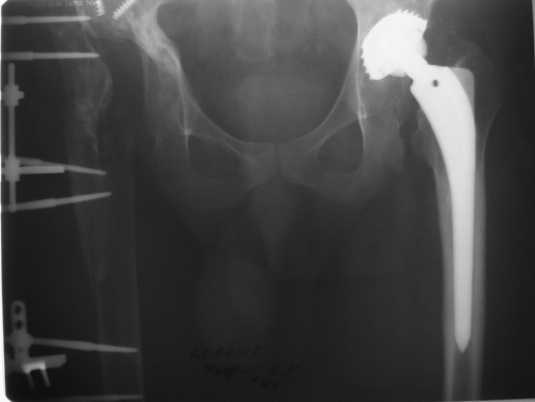

Обращение в нашу клинику в 2008 г. - демонтаж аппарата (рис. 4). Сегодня укорочение 8 см. Слева - протез стабилен, безболезнен.

Что делать дальше?

1. ревизионное ЭП правого ТБС?

2. формирование опорного бедра?

3. Удлинение бедра на АВФ?